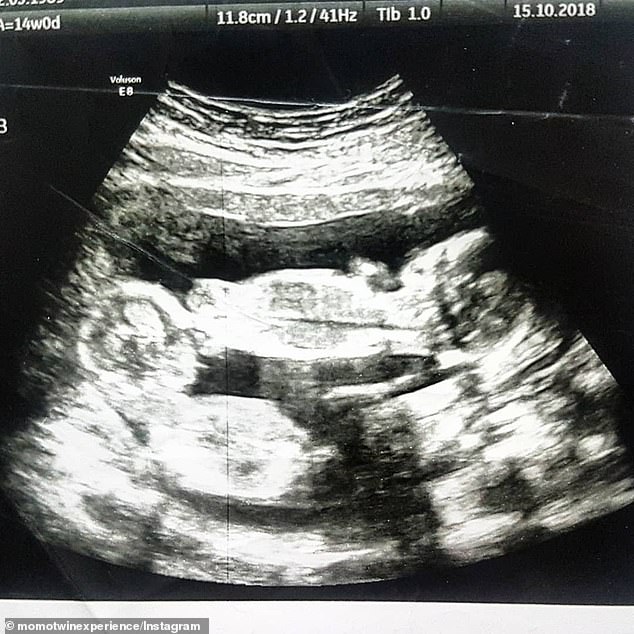

Tvillingarna föddes i samma fosterhinna i livmodern och delade på moderkakan, men de hade varsin navelsträng. Ett sådant tillstånd har stor riks för komplikationer.

Daily Mail skriver att det är 50 procents chans att tvillingar vid de här slaget överlever längre än 26 veckor. Från vecka 10 och framåt krävs det regelbundna ultraljudskontroller för att se till att fostren utvecklas som de ska.